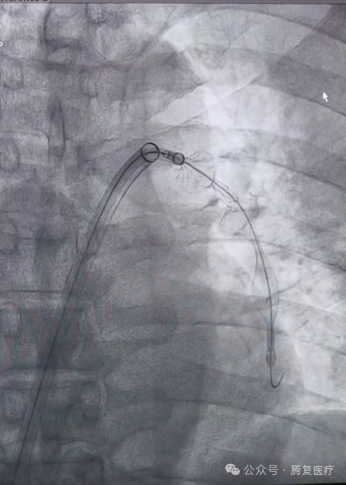

患者仰卧位,局麻后经股静脉穿刺放置血管鞘,引入导丝和导管,建立右心房-右心室-肺动脉通路。韩宝石教授团队将Tendvia®血栓抽吸导管,沿导丝推送至肺动脉。管口贴近血栓处停止,撤出导管芯。并将Tendvia®肺动脉血栓取支架沿导丝通过抽吸导管向前推送,精确导入到患者的肺动脉血栓部位。再回撤输送鞘管,支架自动膨开。连接抽吸器并形成负压,回撤取栓支架的同时旋转开关释放负压。最后,Tendvia®肺动脉取栓支架捕获和收集血栓进入抽吸导管,经负压抽吸同步的作用下,顺利为患者取出了血栓。

手术极大地改善了患者的肺动脉血流和氧合情况,手术圆满成功。全程手术时间约60分钟,患者术后各监测指标平稳,安返病房。